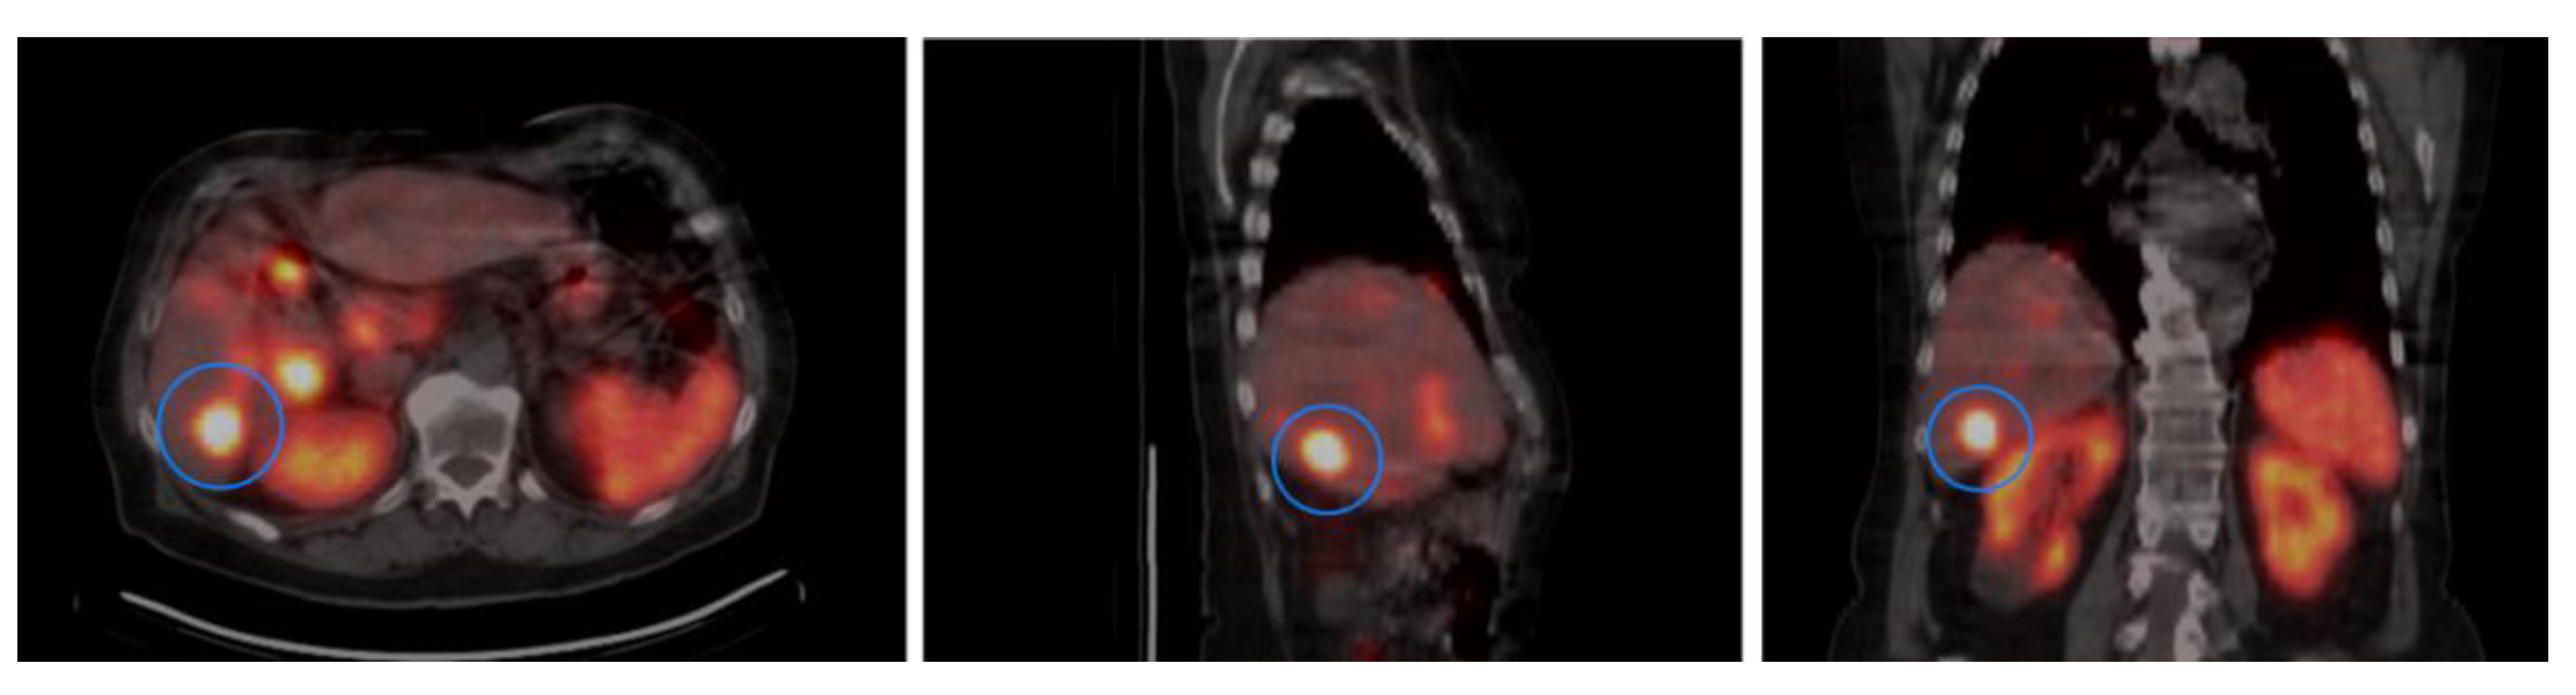

3.4. SSTR2 Expression and Activity Concentration